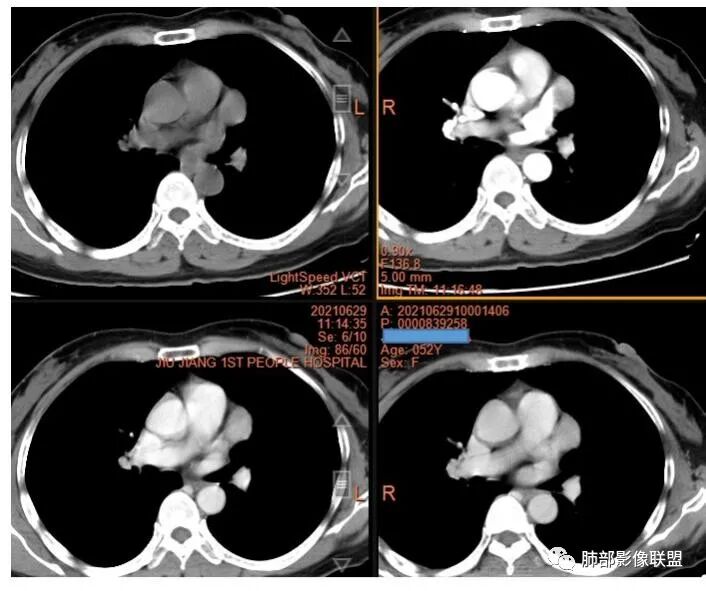

2.左上纵隔肺门夹角处孤立实性密度结节影,边界清楚浅分叶,密度均匀,未见液化、分隔及钙化。

3.动脉期起显著强化并延续至静脉期,强化程度均低于同期胸主动脉。病灶弧形推压左上肺动脉,毗邻左肺上叶支气管但未见侵蚀及突入,相应支气管未见狭窄。

1.纵隔肺门区孤立结节,边界清楚,强化异常显著,首先应当想到的是巨淋巴结增生症(CD),即便病灶延迟强化期相有点长。